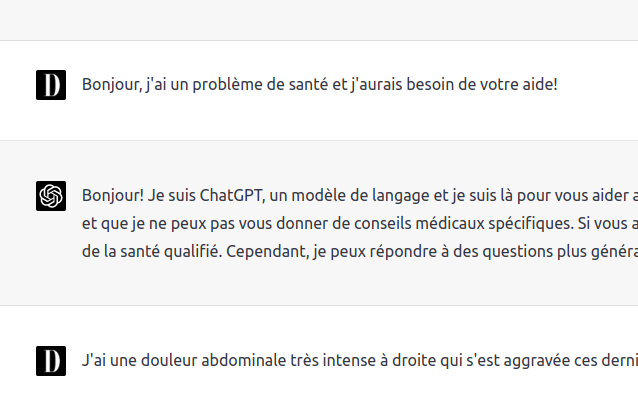

On the data visualization side of my research topics, my students and I regularly collaborate with Quebec media and institutions to produce some interactive visualizations on various news subjects. https://www.oecd-nea.org/jcms/pl_108128/nea-launches-interactive-smr-dashboard- Musical data visualization based on open and linked data.